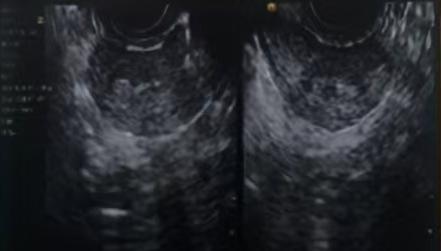

苏州大学附属第一医院超声图示

2024年10月21日本院超声提示:子宫大小37mm*31mm*40mm,子宫全层厚3.5mm,子宫内膜连续性中断,考虑宫腔粘连可能。